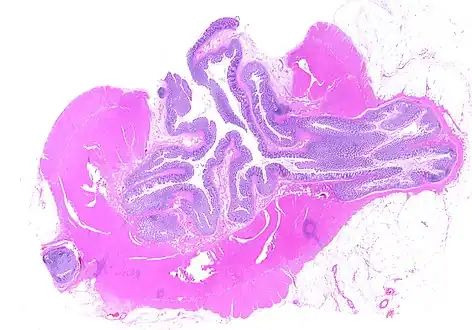

CT scan showing extensive diverticulosis of the sigmoid colon -

Whole slide of a transverse section of the left colon with diverticulosis